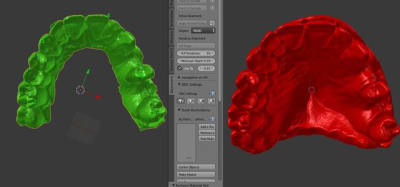

toujours avec mon nouveau jouet, je n'avais jamais testé mais cela fonctionne parfaitement bien

plus besoin de faire couler le plâtre par le labo!!!

un scan ou un cone beam de l'empreinte suffit

très simple ensuite de préparer une provisoire